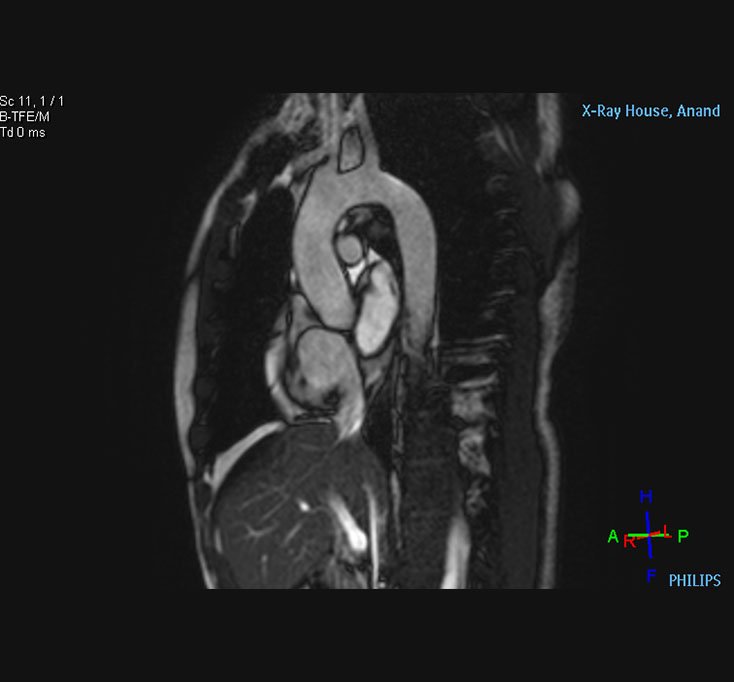

Heart MRI

MRI Aorta